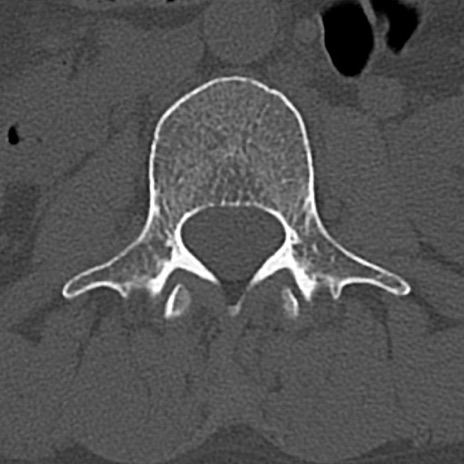

腰椎CT

横断像と矢状断像